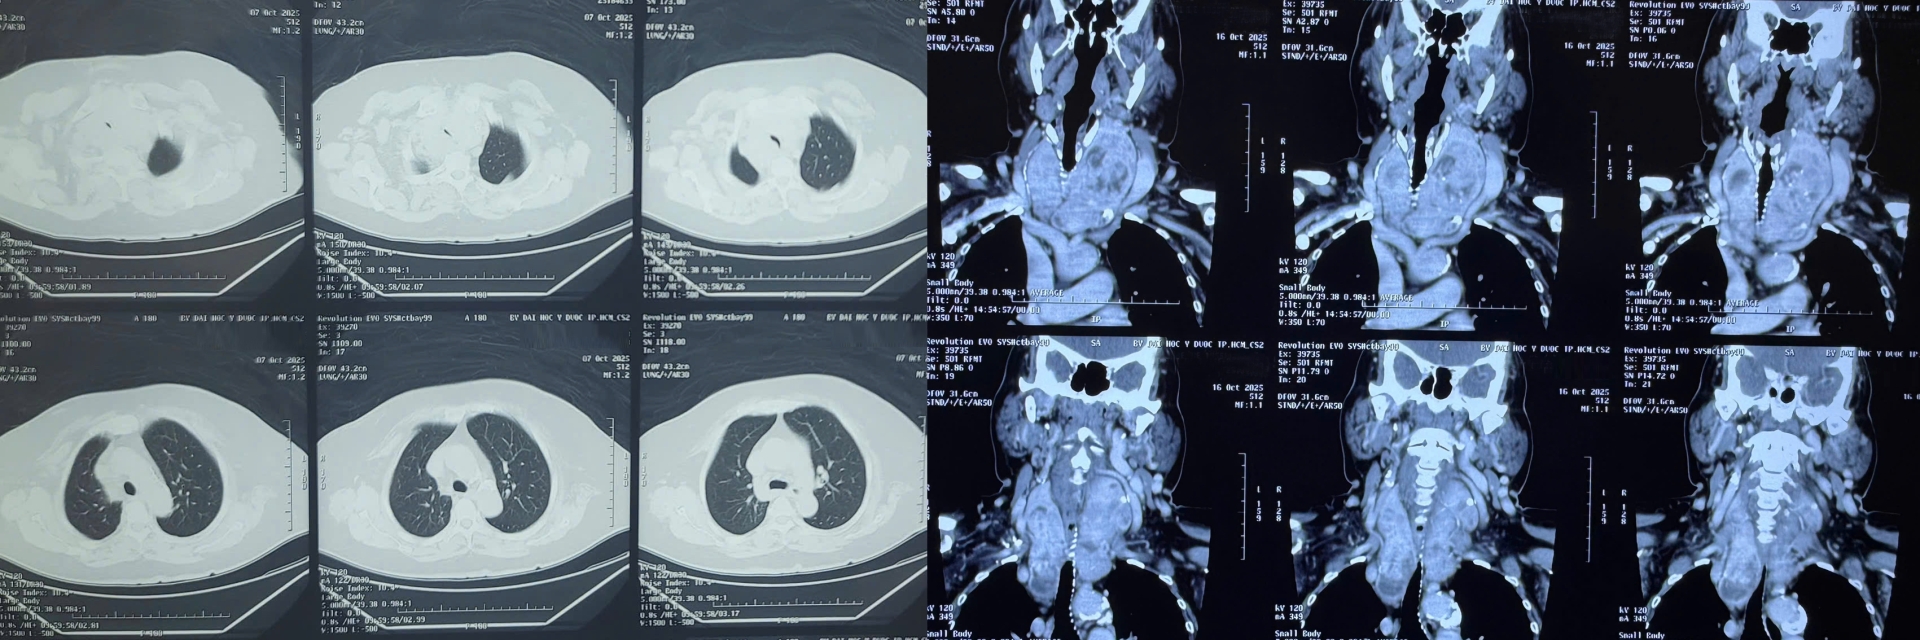

Kết quả kiểm tra cho thấy bà bị bướu giáp thòng trung thất kích thước lớn, chèn ép gần như toàn bộ khí quản, khiến việc hô hấp vô cùng khó khăn.

“Đây là một ca mổ không hề đơn giản. Bướu giáp thòng xuống sâu, ôm sát khí quản và các mạch máu lớn trong trung thất. Chỉ cần sơ sẩy, bệnh nhân có thể mất đường thở ngay trên bàn mổ. Nhưng may mắn là ca phẫu thuật diễn ra thuận lợi, chúng tôi đã lấy trọn khối bướu, giải phóng hoàn toàn đường thở cho bệnh nhân.”

“Đường thở của bệnh nhân bị chèn ép nghiêm trọng, gần như xẹp hẳn ở đoạn dưới thanh quản. Việc gây mê và đặt nội khí quản vô cùng khó khăn, đòi hỏi sự phối hợp nhịp nhàng giữa các bác sĩ phẫu thuật và gây mê để đảm bảo an toàn tuyệt đối. Chúng tôi phải vừa kiểm soát đường thở, vừa theo dõi sát huyết áp, nhịp tim, oxy máu từng giây.